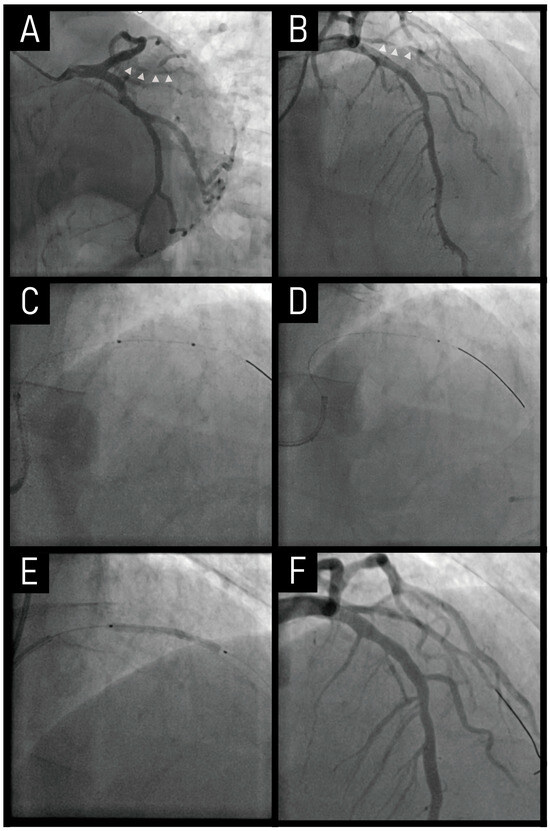

6.1. Case

6.2. Prevalence of Calcification in CTO Lesions

6.3. Clinical Usefullness of RA in CTO Lesions

6.4. Clinical Outcomes of RA in CTO Lesions